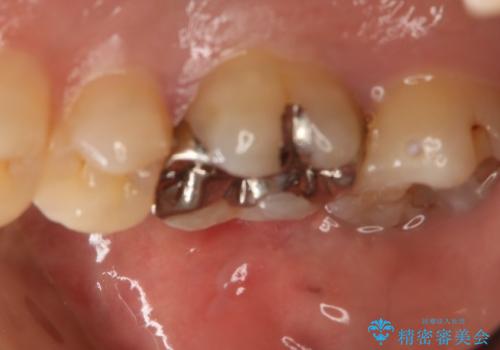

- 右上6番の銀歯をセラミックに変えたいと希望された患者様です。

切削量、形態を考慮し、セラミックインレーでの治療を計画しました。

銀歯と虫歯を除去した上でCRで裏層し形態を整えて印象を行っています。